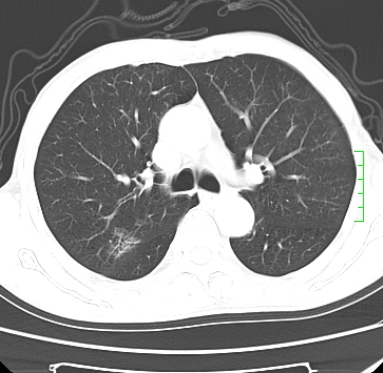

浅分叶、棘突,考虑右下肺周围型肺癌

肿块周围可见局限性气肿,考虑肺癌可能性大。双肺上叶继发型肺结核。

指套征,强化明显,近侧肺组织局限性肺气肿,考虑支气管类癌,慢支、肺气肿、双上陈旧性tb、冠脉钙化。

1)考虑右肺下叶周围型肺癌。2)右肺上叶及左肺感染性病变(结核可能)。3)肺气肿。4)冠状动脉钙化。